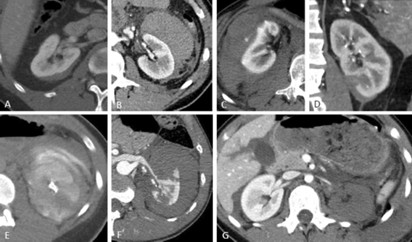

CT Imaging

Management

- Non-operative management in grade I to III renal injuries, regardless of mechanism

- Surgical Exploration in Grade IV and V renal injuries